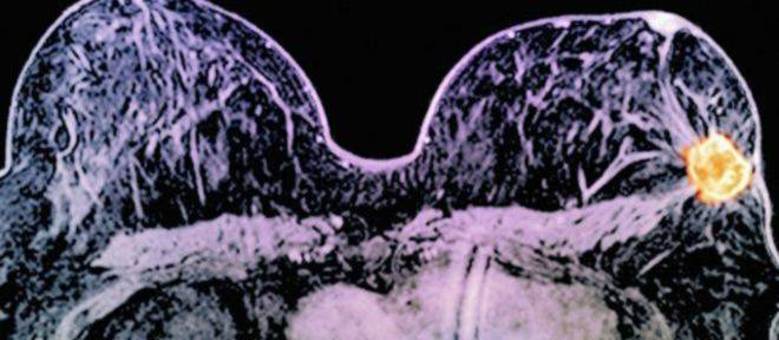

Nova técnica que combina 2 drogas reduz câncer de mama ‘dramaticamente’ em 11 dias

Uma combinação de dois medicamentos pode diminuir muito ou eliminar alguns tipos de câncer de mama em apenas 11 dias, de acordo com médicos britânicos.

As drogas usadas foram lapatinib e trastuzumab, essa última mais conhecida como Herceptin.

As duas têm como alvo a HER2, proteína que acelera o crescimento de alguns cânceres de mama em mulheres.

O Herceptin age na superfície de células cangerígenas, enquanto o lapatinib consegue penetrar dentro da célula para 'desligar' a HER2.

Em menos de duas semanas de tratamento, o câncer desapareceu completamente em 11% dos casos, e em outros 17% ele ficou menor que 5mm.